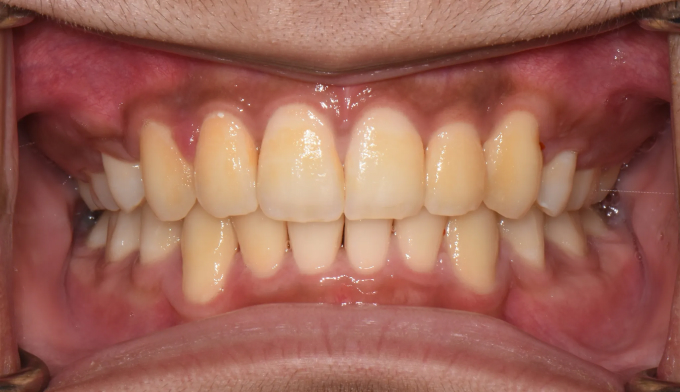

덧니가 심한 학생들, 특히 중,고등학생들을 보면 안타까울때가 종종 있습니다.

조금 더 이른나이에 교정을 시작하였더라면 무리하게 발치하지 않고도 충분히 치아를 가지런하게 할 수 있었을 텐데 라는 생각을 지울수가 없습니다.

이번 케이스도 뒤늦게 송곳니가 덧니로 나오는것을 확인하고 치아교정을 하고자 내원한 중학생입니다.

부족한 공간이 꽤 많고, 입도 돌출되어 보여서 어쩔수 없이 발치교정을 계획하였습니다.

총 치료기간은 23개월입니다.